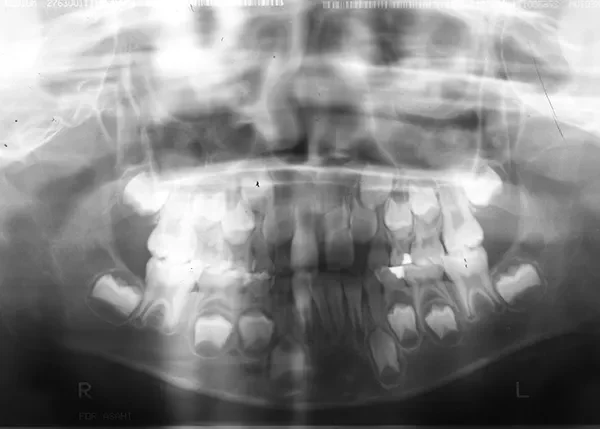

• 初診

初診時年齢 小学校1年生 (男性) 主訴 すきっ歯・ガタガタ・受け口

診断名 叢生・反対咬合・空隙歯列 装置名

特徴 ゆがんで生えている

状態 永久歯が生える隙間がない(叢生)

受け口(下顎前突/反対咬合)

すきっ歯(空隙歯列)

上の前歯が下の前歯より後ろに入って、受け口になっています。

下の歯は永久歯の生えるスペースがないので、オリジナル矯正装置で受け口を治して、永久歯の生えるスペースを作りました。

初診